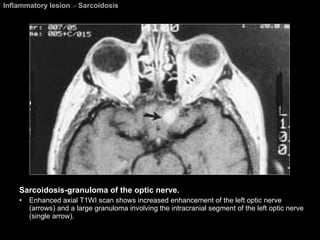

Sarcoidosis A granulomatous systemic disease. Pathology = Noncaseating granulomas  Diagnosis based on biosy. Affecting all races, both sexes, and all ages.  Presentation : asymptomatic with abnormal findings on CXR.   Visual system abnormalities  are the most common extrathoracic manifestations of sarcoidosis.

Sarcoidosis Ophthalmic lesions develop in approximately 25% of patients. Chest abnormalities are found in about 80% of patients with ocular sarcoidosis. Any part of the globe or orbit may be involved.  M/c orbital involvement  =  chronic dacryoadenitis .  May be unilateral and easily mimic a lacrimal gland tumor.

Sarcoidosis A Mikulicz-like syndrome  =  Sacoidosis involvement of bilateral lacrimal glands and salivary gland causings dry eyes and xerostomia. The most common cranial nerves to be affected are the  CN 2 , 7, 5, 8, 3, 6 respectively.

Inflammatory lesion  >  Sarcoidosis Sarcoidosis-granuloma of the optic nerve. Enhanced axial T1WI scan shows increased enhancement of the left optic nerve (arrows) and a large granuloma involving the intracranial segment of the left optic nerve (single arrow).